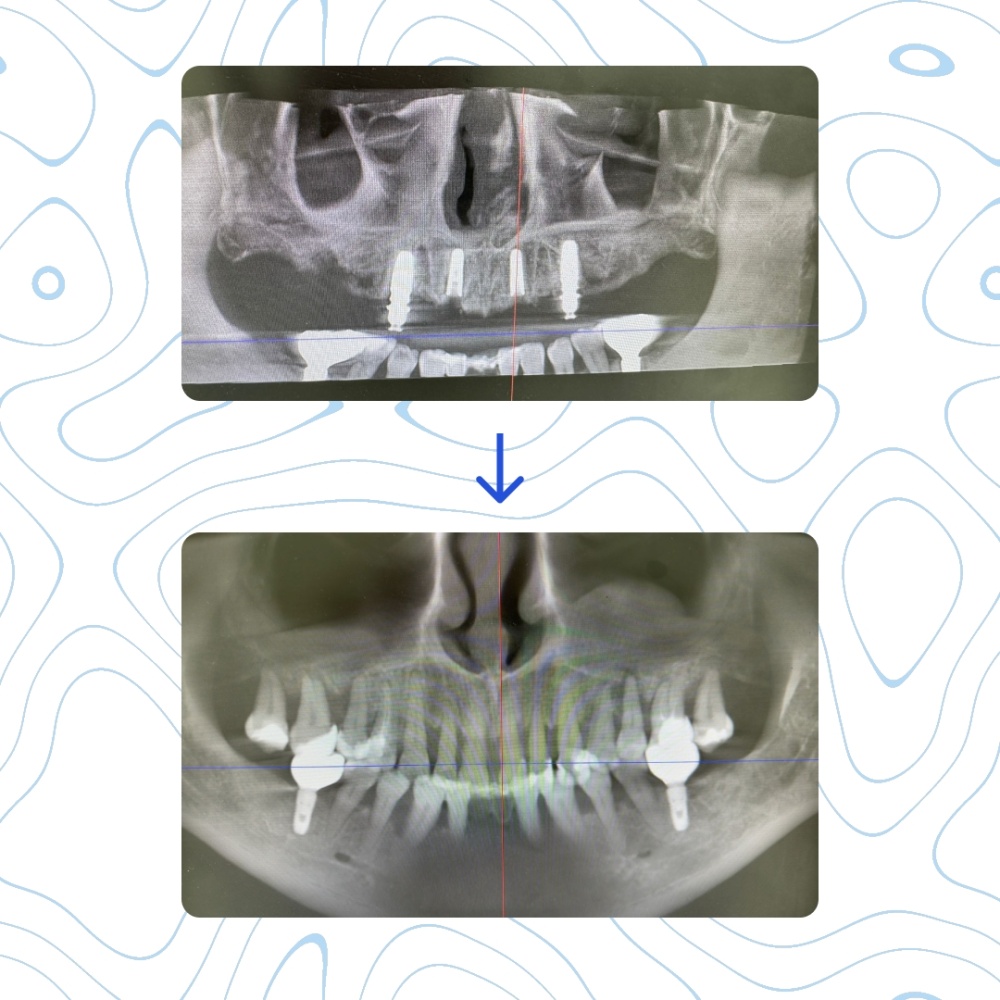

Данный клинический случай - совместная работа врача стоматолога-хирурга Ахметшиной Динары Радиковны и врача стоматолога-ортопеда Галиакберова Ильдара Шафкатовича.